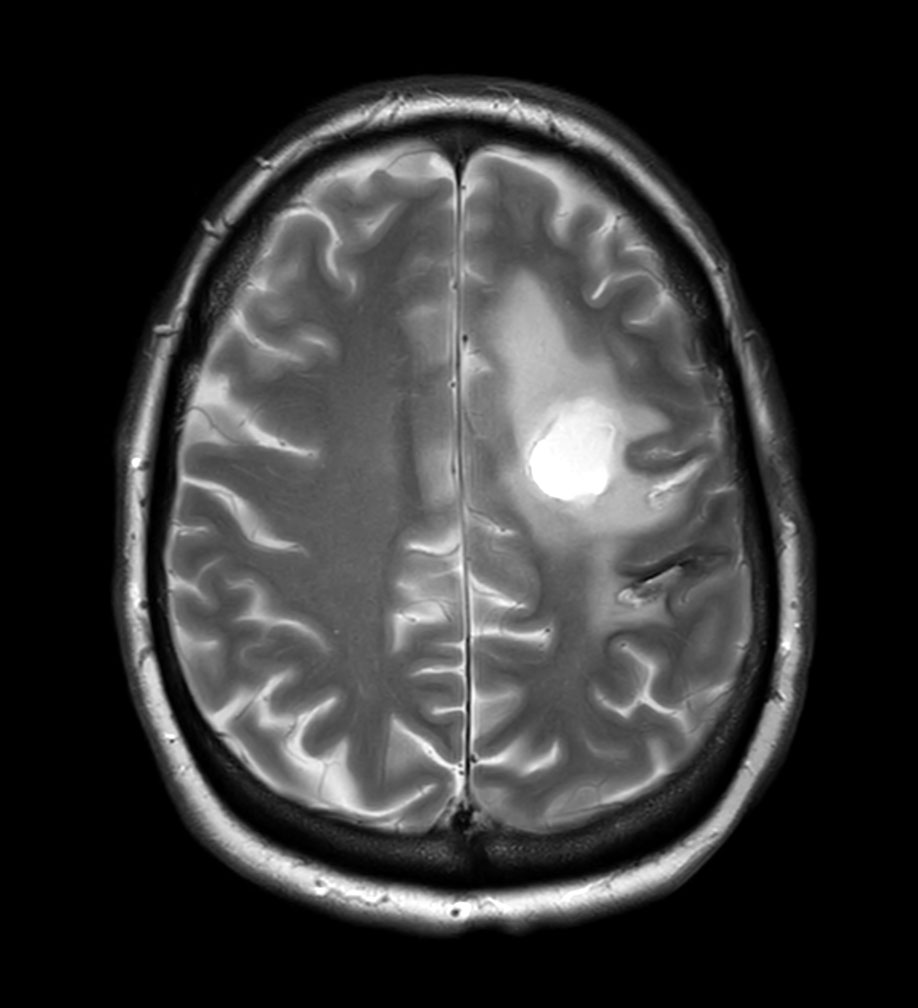

Axial T2w TSE